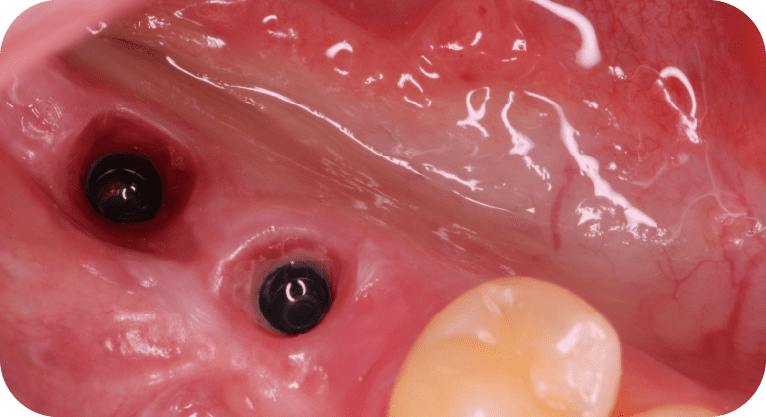

Female patient, “42” years old

Treatment: Dental implant

The patient came to the clinic aer losing two molars due to advanced decay, which affected her chewing function. To restore the edentulous area, dental implants were placed in the corresponding spaces, restoring chewing ability, preventing bone loss, and maintaining the alignment of adjacent teeth, achieving satisfactory functional and aesthetic results.